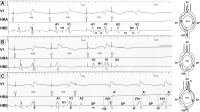

Dekrementale Leitung - AVN

Abbildung 5: Veranschaulichung der dekrementalen Leitung im AVN. Die EKG-Aufzeichnungen A, B und C zeigen eine Vorhofstimulation mit einer Basiszykluslänge von 500 msec (S1-S1). Bei dieser Zykluslänge besteht ein A1-H1-Intervall von 170 msec (entspricht der AV-Knoten-Leitungszeit) und ein H1-V1-Intervall von 42 msec (entspricht der Leitungszeit des HPS bis zur Ventrikelaktivierung). Ein vorzeitiger Stimulus (S2) mit einem Kopplungsintervall von 300 msec (S1-S2) benötigt eine längere Leitungszeit (260 msec) im AVN (A2-H2), die Überleitungszeit im HPS bleibt praktisch unverändert (46 msec, H2-V2). Bei Verkürzung des S1-S2-Intervalls auf 290 msec verlängert sich die AH-Zeit auf 285 msec bei unveränderter HV-Zeit. Ein noch kürzer gekoppelter Stimulus (280 msec S1-S2) wird im AVN blockiert (A2 ohne H2). Die ERP des AV-Knotens ist bei diesem Beispiel 280 msec. Unten links ist eine schematische Darstellung der AV-Überleitungszeiten abgebildet. Je kürzer die Kopplungszeit (R-P), umso länger wird die Überleitungszeit (P-R). Es besteht ein annähernd lineares Verhältnis im Rahmen eines breiteren Spektrums. Aus [19].